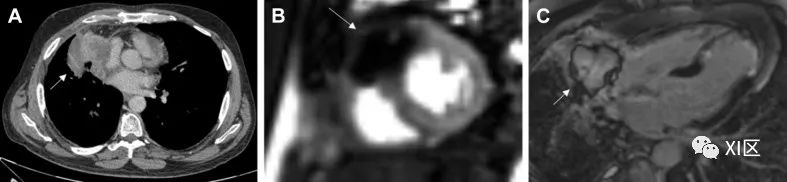

心黏液瘤(图 2)是最常见的 PCT,据信来源于间充质细胞前体。它们形成腔内肿块,最常见于左心房,通过柄与卵圆窝相连,但也可能出现在儿童的右心房。其他解剖学来源包括心房游离壁和二尖瓣瓣叶;但这些来源的可能性较小。有 7% 的患者在就诊时被发现患有心脏黏液瘤,与卡尼综合征(一种多发性肿瘤和皮损综合征)有关联。确诊时的平均年龄为 50 岁,约 70% 的患者为女性。

图 2 黏液瘤53 岁男性,左心房黏液瘤,曾出现栓塞事件。(A)经胸超声心动图检查发现附着在房间隔上的巨大移动肿块(白色箭头)。(B)心脏CT中看到的表面光滑的低衰减、轮廓清晰的肿块(黑箭头)。C)CMR晚期钆成像中左心房肿块的异质摄取(白箭头)。

在超声心动图检查中,心脏黏液瘤通常表现为一个移动的肿块,通过一个柄附着在心内膜表面,通常从卵圆窝产生。RT3DE 可通过裁剪功能和仔细使用数字分析来剖析病灶,从而帮助进行梗阻分析和肿块异质性分析。可能需要进行 TEE 检查,以更好地观察植入部位,并确定是否有可能扩展到肺静脉或腔静脉。在心脏 CT 上,黏液瘤通常表现为腔内低衰减肿块,表面光滑或略带绒毛。约 14% 的患者可见钙化,右侧病变更常见。动脉期造影剂强化通常不存在,但在较长的时间延迟下进行的检查中可发现异质强化。电影图像的重建有助于评估病变的移动性和附着情况;但这往往并不可靠,尤其是对于茎干较短的肿瘤。在 CMR 上,T1 和 T2 加权图像上通常会出现异质外观,这是由于黏液瘤的成分所致,黏液瘤往往含有不同数量的黏液组织、出血组织、骨化组织和坏死组织。延迟强化通常是斑片状的。在稳态自由进动序列上,二尖瓣或三尖瓣在舒张期脱垂可能提示有蒂病变的附着点。